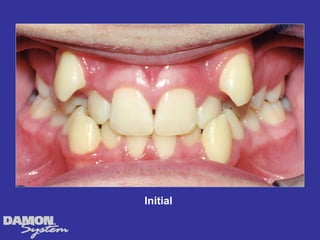

M.J. 14 yrs 6mos Class I severe crowding, deep bite, all Initial cuspids blocked out.

Initial 16 yearsโ€“ 5 months Class II, severe crowding, bilateral posterior crossbite